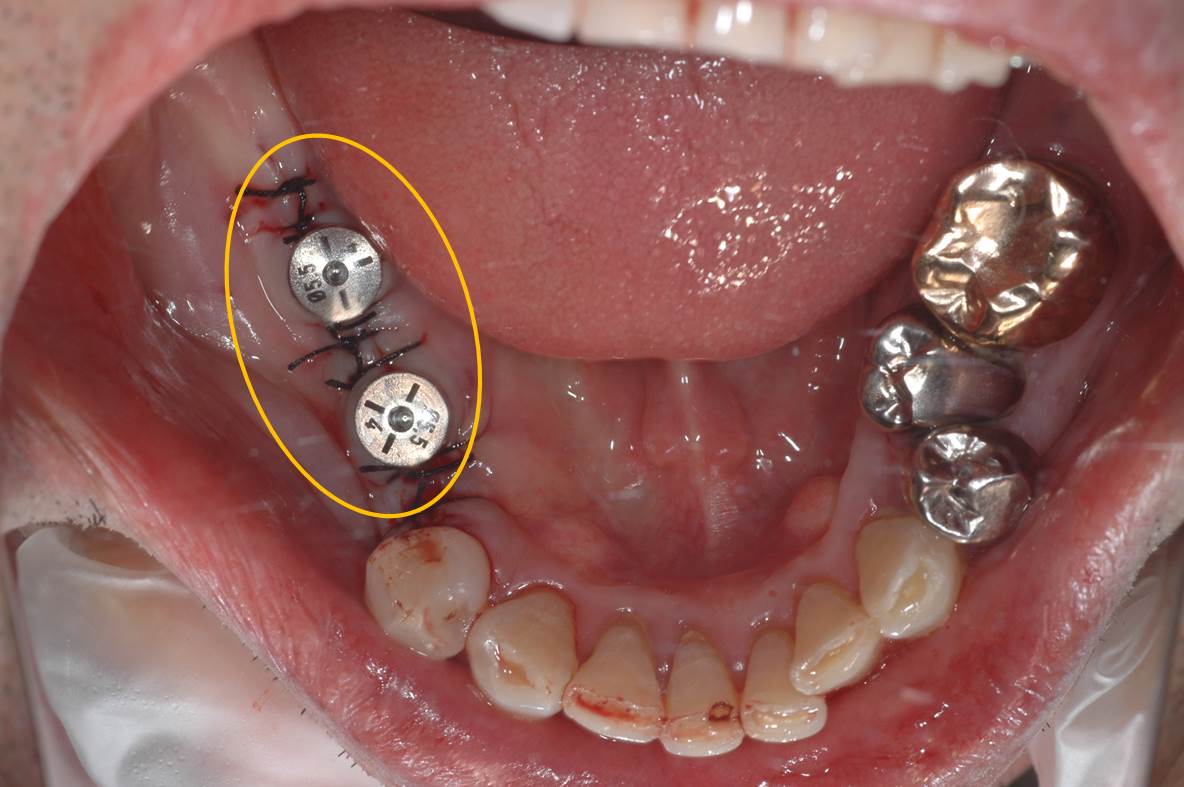

インプラント埋入直後の写真です。

術後の口腔内写真です。